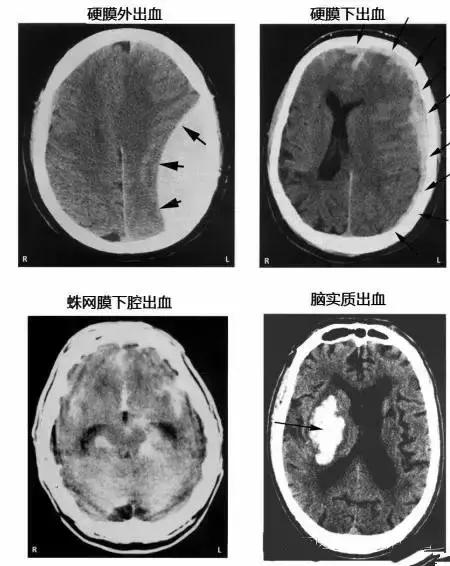

各种颅内出血

13

几种类型脑出血的CT表现

15